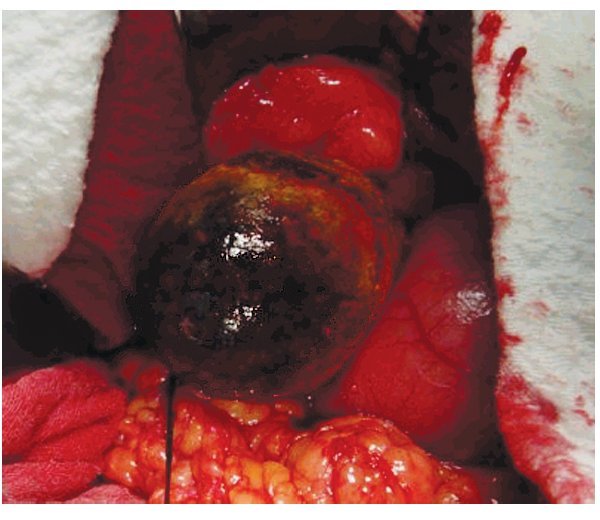

Se trata de paciente femenino de 75 años de edad, la cual acude al servicio de urgencias por presencia de vómitos en varias ocasiones de contenido gástrico, intolerancia a los alimentos, malestar generalizado y datos francos de deshidratación secundaria, con 15 días de evolución desde el inicio de su padecimiento. La paciente tiene antecedentes de diabetes mellitus, hipertensión arterial y refiere gastritis crónica en tratamiento. A su ingreso se encuentra orientada, conciente y sin datos de alarma abdominal, por lo que es internada para su estudio y estabilización con sospecha de cuadro de estenosis péptica pilórica. Se coloca sonda nasogástrica drenando aproximadamente 3 L de material gástrico espeso y restos de alimentos. Laboratorios a su ingreso con hemoglobina de 10 mg/dL, leucocitosis de 13,000 mm3, glucosa 96 mg/dL, urea 30 mg/dL, creatinina 1.8 mg/ dL. Una vez con la paciente en mejores condiciones, se decide realizar panendoscopia encontrando un cálculo biliar gigante impactado en el bulbo duodenal (Imágenes 1 y 2) realizándose múltiples maniobras de extracción con pinzas de cuerpo extraño, las cuales no fueron exitosas. Se realizó ultrasonido demostrando la presencia del cálculo impactado en duodeno, no se apreció dilatación de vías biliares (Imagen 3). Con estos hallazgos se decide someter a la paciente a cirugía, encontrando la presencia de un cálculo biliar gigante dentro del bulbo duodenal con vesícula biliar escleroatrófica, se realiza duodenotomía y extracción del cálculo con duodenorrafia en 2 planos tipo Heineken-Mikulicz sin incidentes transoperatorios (Imágenes 4, 5 y 6) y con adecuada evolución, siendo egresada al octavo día del posoperatorio.

Imagen 1. Toma endoscópica que muestra la obstrucción duodenal por cálculo biliar.